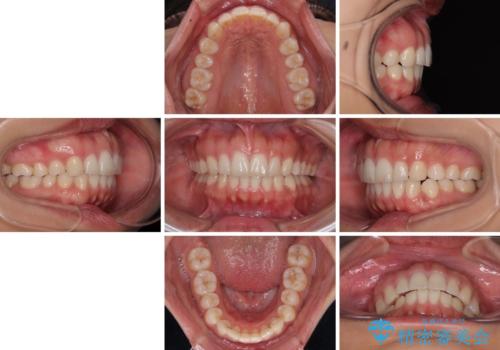

【モニター】突出した前歯 補助装置を併用したインビザライン矯正

- 上下前歯が非接触となり、前方に突出していることを気にして来院された患者様です。

咬合力が強く、全体的に歯がすり減っているため、インビザライン単独での上顎歯列移動は困難と判断し、補助装置により上顎歯列を後方移動させ、その後インビザラインにて仕上げていくこととしました。

補助装置なしでも改善できる可能性はありましたが、補助装置で確実性を上げ、短期間できっちりと仕上げることができました。